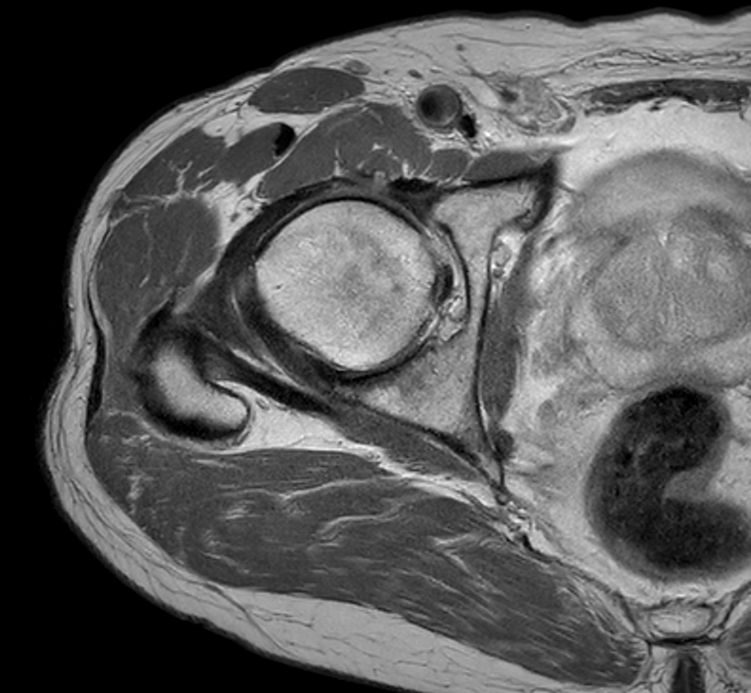

Axial PDw TSE

Axial PDw TSESmartSpeed

Axial PDw TSESmartSpeed High Resolution